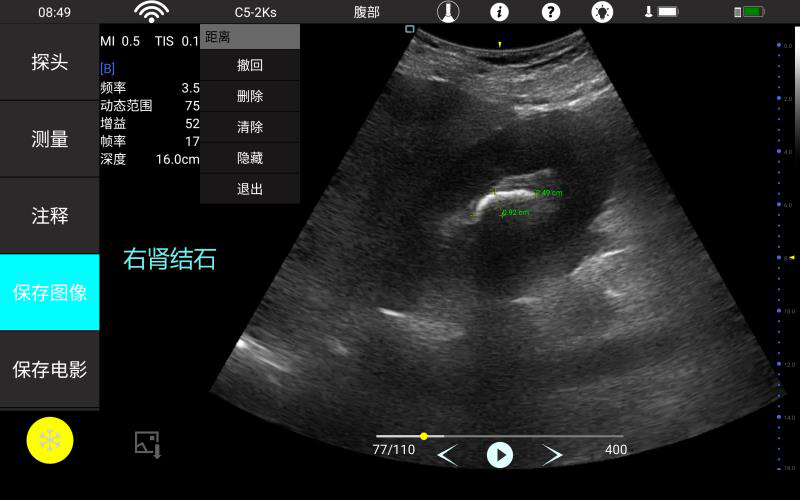

腹部

肾脏

妇科产科

心脏

肺等